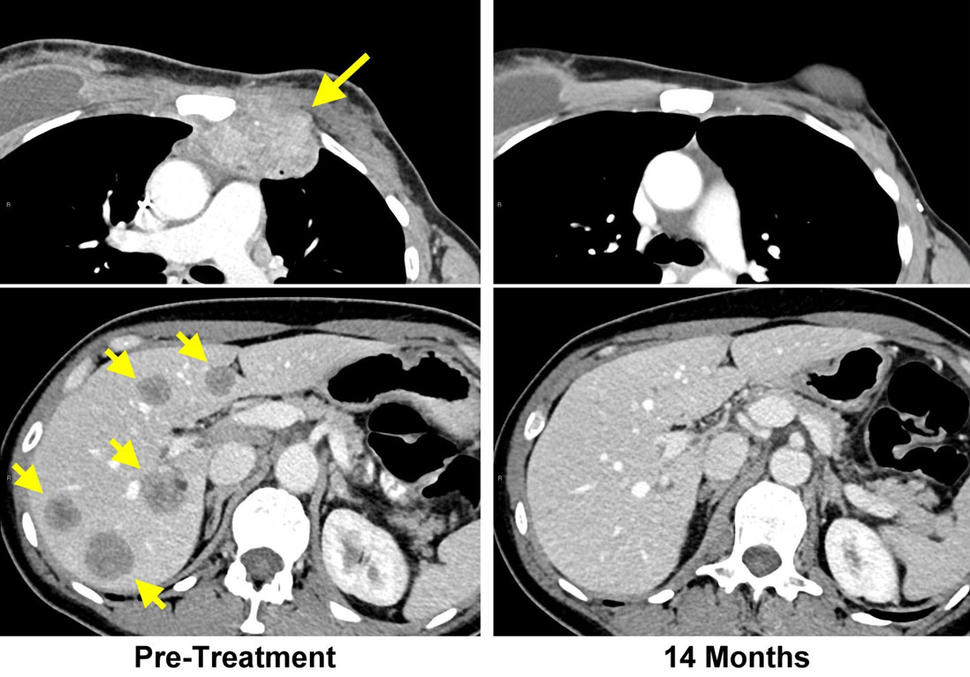

Left: CT scans of a woman with breast cancer before TIL therapy show a lesion invading the chest wall (top) and metastatic lesions in the liver (bottom). Right: Scans 14 months after treatment show all lesions have disappeared.

A novel approach to immunotherapy developed by researchers at the National Cancer Institute (NCI) has led to the complete regression of breast cancer in a patient who was unresponsive to all other treatments. This patient received the treatment in a clinical trial led by Steven A. Rosenberg, M.D., Ph.D., chief of the Surgery Branch at NCI’s Center for Cancer Research (CCR), and the findings were published June 4, 2018 in Nature Medicine. NCI is part of the National Institutes of Health.

The researchers then tested different TILs from the patient to find those that recognized one or more of these mutated proteins. TILs recognized four of the mutant proteins, and the TILs then were expanded and infused back into the patient. She was also given the checkpoint inhibitor pembrolizumab to prevent the possible inactivation of the infused T cells by factors in the tumor microenvironment. After the treatment, all of this patient’s cancer disappeared and has not returned more than 22 months later.